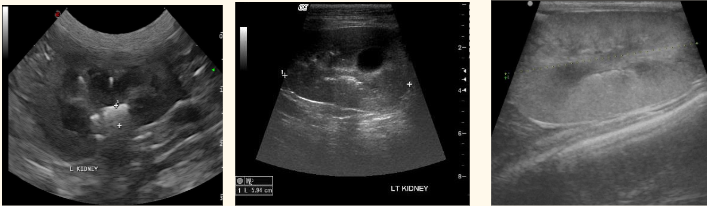

what are these 3 common findings in the kidney

-renoliths

-renal cysts

-CKD